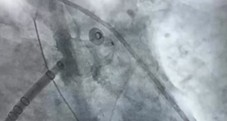

团队率先为患者实施全麻下房颤射频消融术,随后,经ICE实时引导,将Watchman FLX封堵器精准释放在左心耳开口处,术后造影及超声验证封堵完全无残余分流。

Carto三维系统结合ICE技术,既能提升消融精准度、降低并发症,又可动态评估左心耳形态,确保封堵器完美贴合,尤其适用于左心耳结构复杂或需个体化治疗的患者。